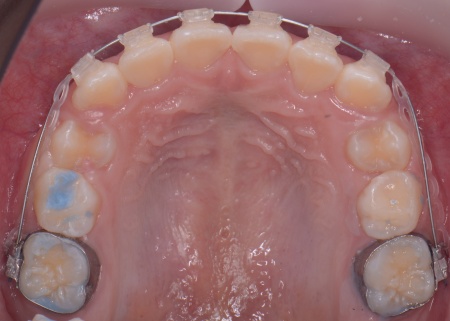

10歳女の子 成長期を利用した小児矯正治療で八重歯を改善した症例

拝見したところ、上の犬歯が歯列の外側に飛び出すように生えている、いわゆる八重歯でした。

さらに、上下の歯全体がデコボコに生えている「叢生(そうせい)」と呼ばれる状態で、これは歯が正しい位置に並ぶためのスペースが不足していることが原因だと考えられます。

まず、上顎に顎の骨を広げるための固定式の矯正器具「急速拡大装置」を、下顎には歯並びの幅を広げるための「リンガルアーチ」を装着します。

治療を進めた結果、上顎は約6mm拡大し、歯が並ぶためのスペースを確保することができました。

上前歯6本と左右の奥歯の表面に「ブラケット」と呼ばれるボタン状の装置を設置し、そこにワイヤーを通して歯を少しずつ動かしていきました。

この装置は、歯の高さや位置のばらつきを整える「レベリング」を行うためのもので、拡大によって確保したスペースを活かしながら、歯並びを段階的に整えます。